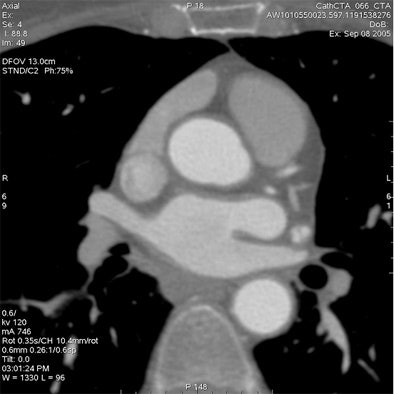

Minimize field-of-view

Most CT scanner manufacturers now offer bowtie filters, which reduce the maximum field-of-view (FOV) allowable while cutting the radiation dose, Budoff said.

For example, using protocol parameters of 600 mA, 120 kV, and a heart rate of 60 bpm, a small cardiac bowtie filter (standard 25-cm FOV) permits cardiac images to be acquired at dose-length product (DLP) of 474 (8.0 mSv), Budoff said. A medium bowtie filter (allowing reconstruction to 36-cm FOV) affords a dose of 791.4 DLP (13.4 mSv).

The heart fits in a 25-cm field-of-view, permitting the use of a small bowtie filter in medium-sized and sometimes even larger patients, Budoff said. "We're only worried about the heart," he said.

"What I call a cardiac CT always includes the great vessels, the myocardium, the left and right atrium, and pericardium," Budoff said. "I'm never only interested in the coronary anatomy. But in cardiac CT, I'm never interested in the lung. If I'm interested in the lungs, I can do a dedicated lung scan for an additional 0.7 mSv of radiation and have it interpreted separately and done properly."